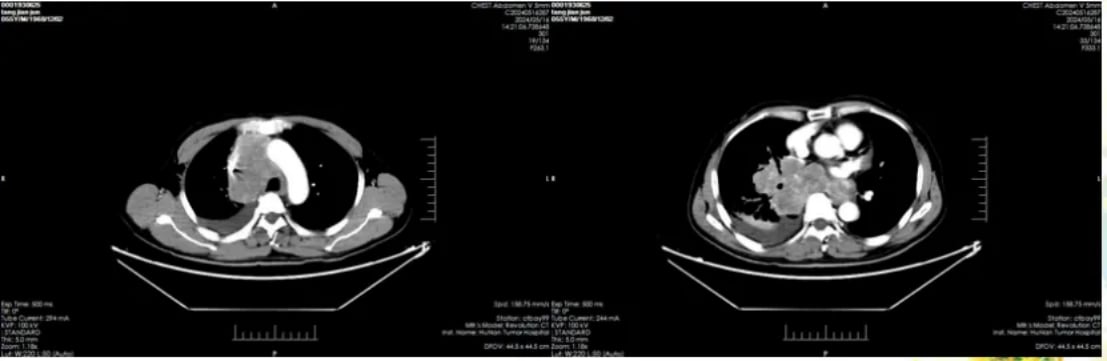

肺部病灶变化:

治疗前(2024-5-14),右肺门区可见明显肿块。治疗后(2024-7-17),右下肺门区肿块较前显著缩小,阻塞性肺炎及肺不张得到缓解,纵隔转移淋巴结也明显缩小,胸腔积液减少。

图1:治疗前肺部影像

图2:治疗后肺部影像